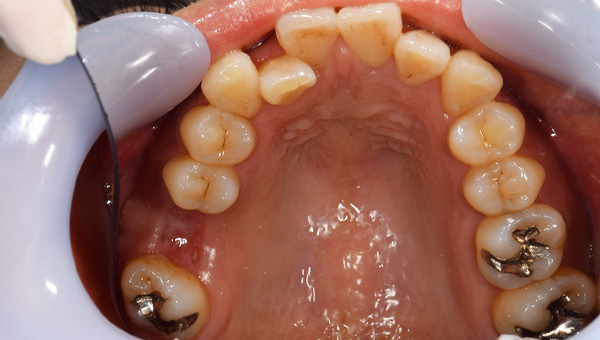

移植後

根管治療後

説明:

移植をし終わったところです。ワイヤーで3週間ほど固定します。その後根管治療を行い、かぶせ物をかぶせて治療終了になります。